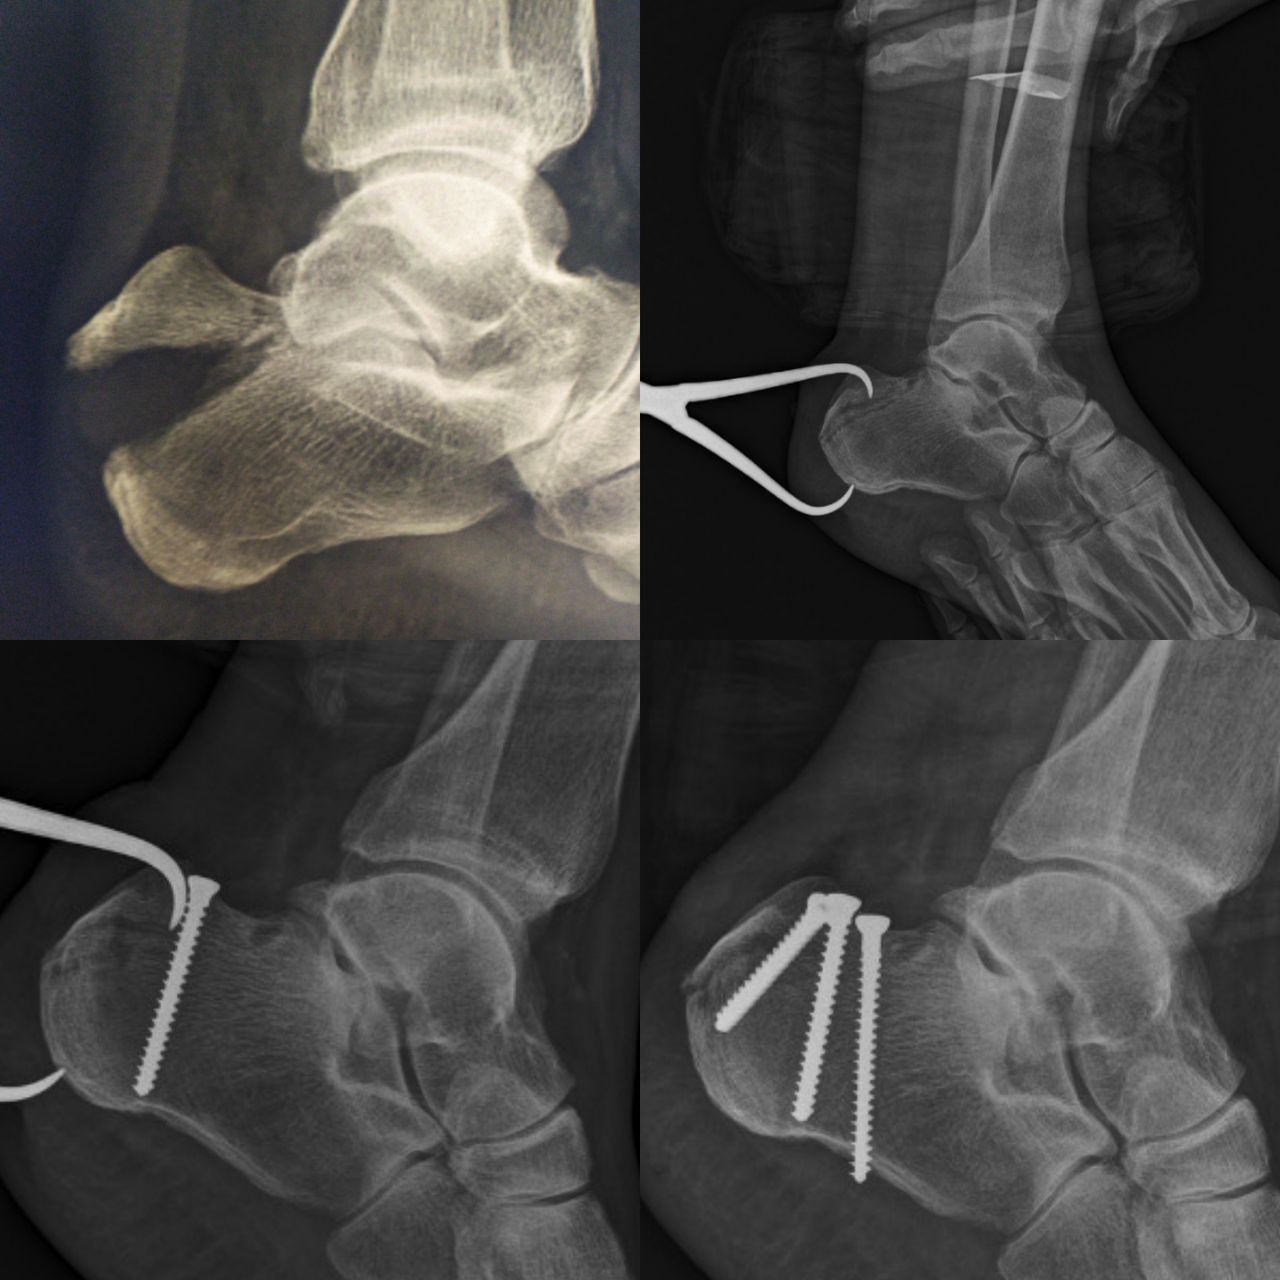

Querido paciente, soy Traumatólogo y Ortopedista egresado del Hospital Central de la Universidad Autónoma de San Luis Potosí, donde me especialicé a tratar todo tipo de problemas en el sistema musculoesqueletico, desgaste, fracturas, luxaciones, lesiones ligamentarias de (hombro, codo, mano, muñeca, columna, cadera, rodilla, pie y tobillo)

Posteriormente hice una Alta Especialidad en el Hospital de la Cruz Roja Mexicana de Mérida Yucatán, donde aprendí a tratar patología específica y compleja de pie y tobillo ( desgaste de tobillo, espolón Calcaneo y Fascitis plantar, Hallux Valgus (Juanetes), Pie plano del niño y del adulto, pie cavo, deformidades de los dedos menores del pie, pie diabético, artropatía de charcot, lesiones del tendón de Aquiles, lesiones deportivas.

Tuve la oportunidad de estar en "Centre Hospitalier de Dax - Côte d'Argent" en FRANCIA, donde aprendí a utilizar los mejores y más novedosos materiales para tratar todo lo relacionado a fracturas, columna y artroscopia.